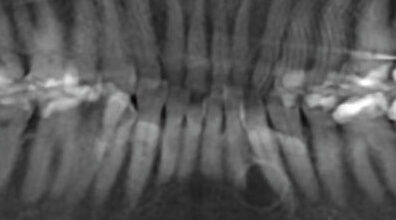

A 9-year-old girl presented to the oral surgeon, referred by her family dentist, because of a lesion in the right posterior maxilla.